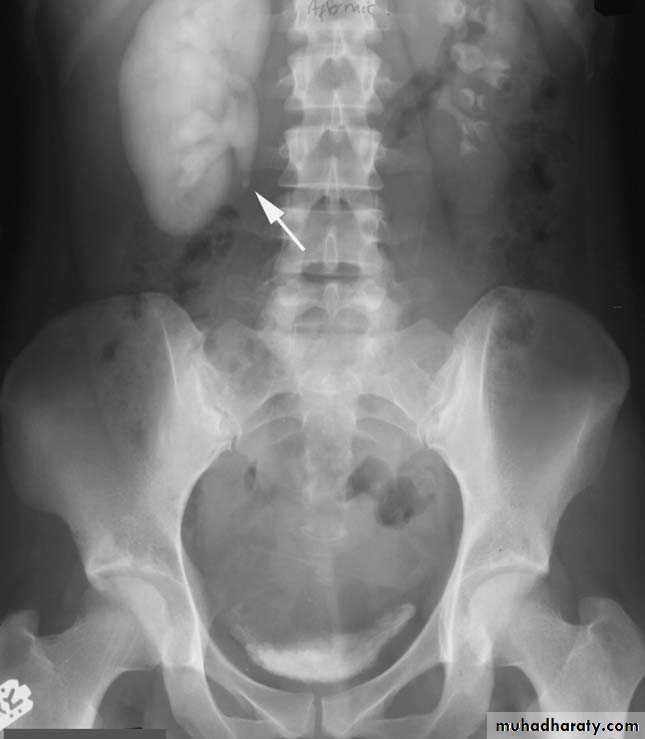

Radiograph from a retrograde pyelogram of the left kidney reveals a multilobulated filling defect (arrow) in the left renal pelvis. Biopsy confirmed transitional cell carcinoma.